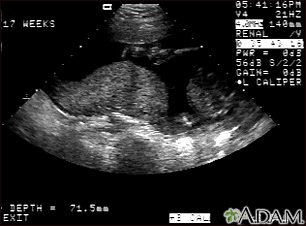

Ultrasound, normal placenta - Braxton HicksBackUltrasound, normal placenta - Braxton HicksThis is a normal ultrasound performed at 17 weeks gestation. It shows the placenta during a normal (Braxton Hicks) contraction. Throughout the pregnancy, the uterus periodically contracts to facilitate better blood flow through the placenta and the fetus. In this ultrasound, the placenta can be seen as the mound-shaped object in the middle of the screen. At the bottom of the image, the mother's vertebra can be seen as a round object. When the uterus is not contracting, the placenta would appear much flatter. E-mail FormEmail ResultsName:Email address:Recipients Name:Recipients address:Message: